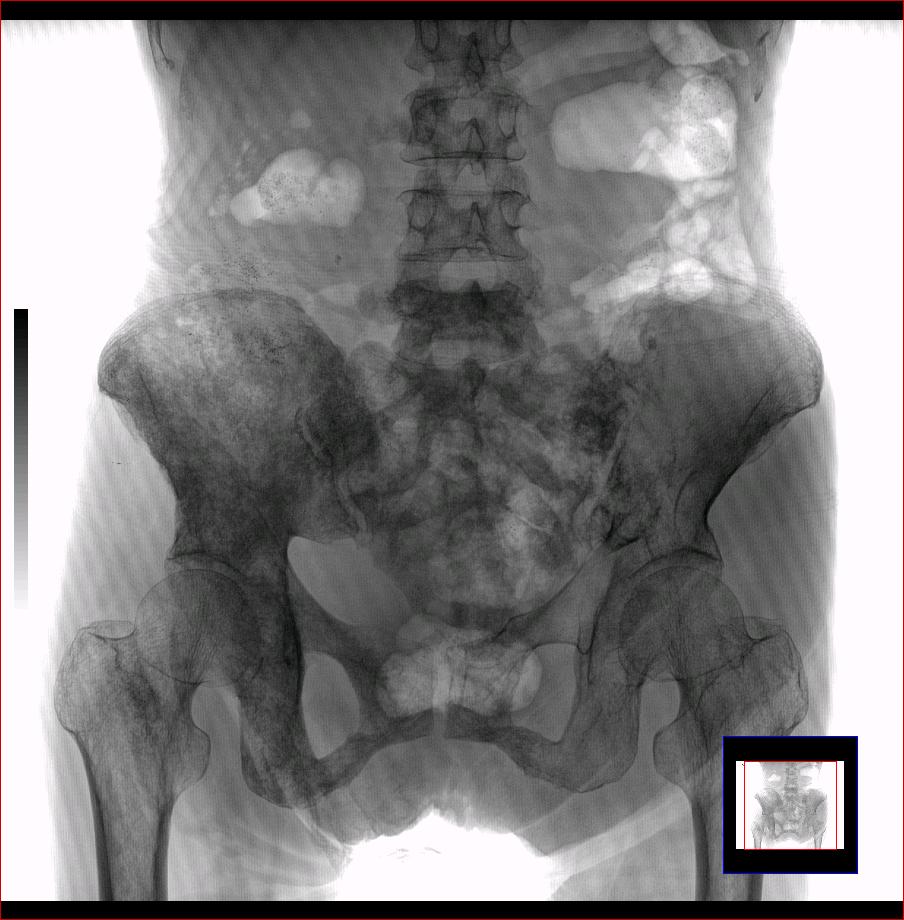

以下是引用ybing在2007-8-22 20:31:00的发言:[br]左侧髂骨溶骨样破坏;软组织肿块形成;其内未见肿瘤骨考虑纤维肉瘤或滑膜肉瘤不除外转移瘤

以下是引用qiushi在2007-8-22 21:39:00的发言:[br]双侧髂骨、骶骨侧快呈溶骨样骨质破坏,边缘模糊,左侧髂骨见骨折线,左侧髂部见软组织块影。考虑骨纤维肉瘤(中央型)伴病理性骨折,不排除骨髓瘤。建议本--周氏蛋白检查。[br] 鉴别点:[br] 骨纤维肉瘤,中央型者示边缘模糊的囊状溶骨破坏,一般无骨膜反映,可膨胀变形,突破骨皮质可形成软组织肿块,或并发病理性骨折。[br] 骨髓瘤,常表现为广泛的骨质疏松,皮质变薄或破坏,呈粟栗状、穿凿状、鼠咬状骨质破坏,边缘清晰,周围无硬化。[br] 骨转移瘤(溶骨型),表现为虫噬样、泡沫状圆形或卵圆形破坏区,很少出现软组织块影。[br][br][本贴已被 qiushi 于 2007-8-23 6:20:19 修改过]